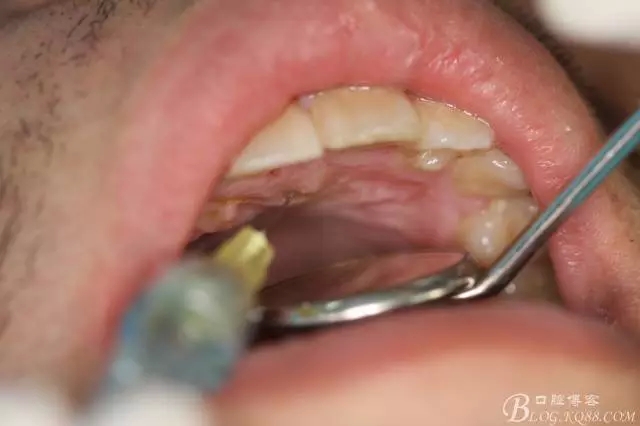

圖3.唇、腭側(cè)局部浸潤(rùn)麻醉

圖4.唇側(cè)角形切口